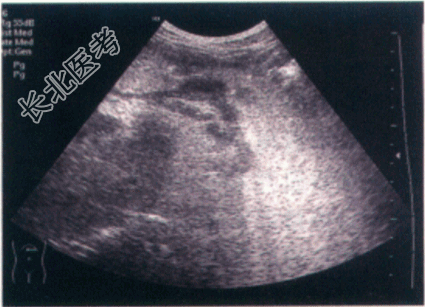

- [材料题] 患者,男性,70岁,因"中上腹不适1年"就诊,伴反酸、嗳气,胃纳差,消瘦,半年内体重下降7.5kg。既往有胃溃疡病史。体格检查:患者腹部平坦,未见胃肠型、蠕动波及腹壁静脉曲张;全腹无压痛、反跳痛、肌紧张,Murphy征(-),肝脾肋下未触及,全腹叩诊呈鼓音,移动性浊音(-),肝区叩击痛(-),肠鸣音正常。实验室检查Hb92g/L。影像资料如下:

- 简答题1、该患者的最后诊断是什么?

- 简答题2、该患者胃癌的扩散情况如何?

- 简答题3、该患者是否需要进行手术治疗,以及手术的可行性如何?